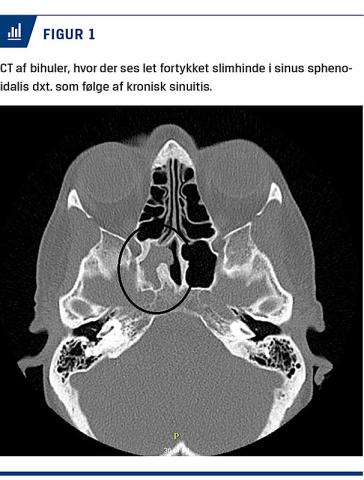

Der blev foretaget relevant biokemiske undersøgelser med normale fund. CT af hjernen og ansigtet og MR-skanning viste en anelse polyplignende slimhinde og fortykkelse af sinus sphenoethmoidalis på højre side (Figur 1). Der var ingen tegn på gennembrud til øjenhulen. Skanningerne viste, mod forventning, ingen patologisk opladning i parenkym, meninges eller kranienerver.